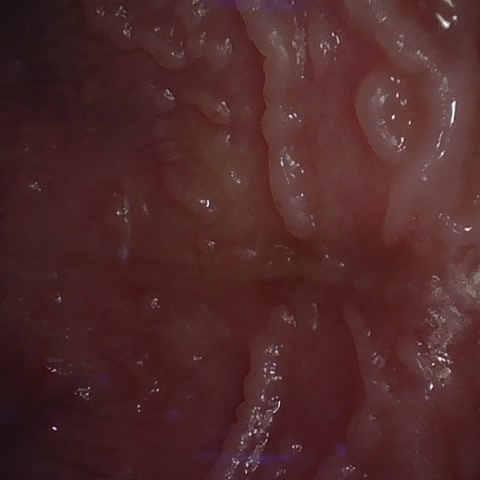

Image 712 / 1103

NHD39174

Annotated as "Good"

Original Image Rendering Image